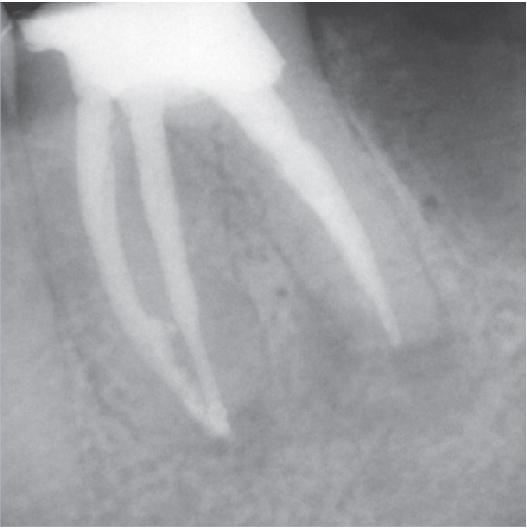

Before

Before Root Canal treatment